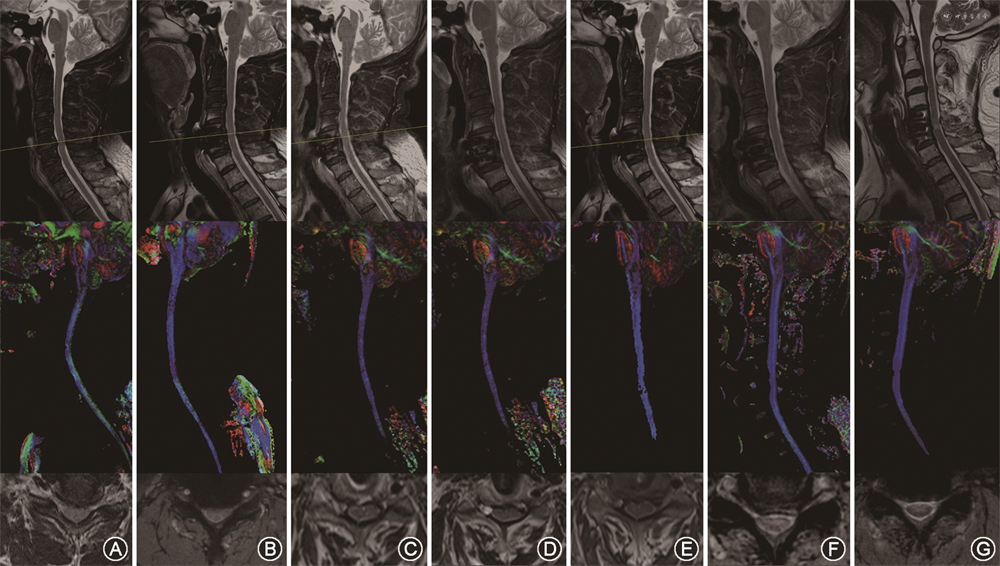

患者女,59岁。因双上肢麻木无力2年,伴双下肢足底踩棉感6个月收入住院。术前MRI检查发现C4/5节段颈椎管狭窄,结合病史及查体表现考虑CSM诊断明确。术前行颈椎DTI扫描发现FA-MCL=0.425±0.021,术前mJOA评分10分。于本院行ACDF术,手术过程顺利,术后症状缓解。术后3个月复查时FA-MCL为0.475±0.012,mJOA评分14分,改善率57.1%(图3)。患者术后各时间点随访各指标见表2。

弥散加权图像重建后,利用DTI Studio计算FA和特征值(λ1、λ2、λ3)。首先,利用矢状面T2WI来识别狭窄节段。然后在轴向T2WI和b0图像脊髓受压最终水平上绘制感兴趣区(ROIs)(图1)。ROI由2名本院拥有30年以上经验的脊柱外科主任医师手动划取,在轴向T2WI多快速场回波图像作为区分CSF和脊髓边界的参考,并选取T2WI多快速场回波上颈脊髓压迫最严重节段(MCL)的压迫最严重层面(同一节段层面数为5层选取中间层面即第3层)。DTI参数例如FA等值,从相应ROI中提取并计算平均值,若差异超过20%则请第3名上级主任医师进行测量(图1)。